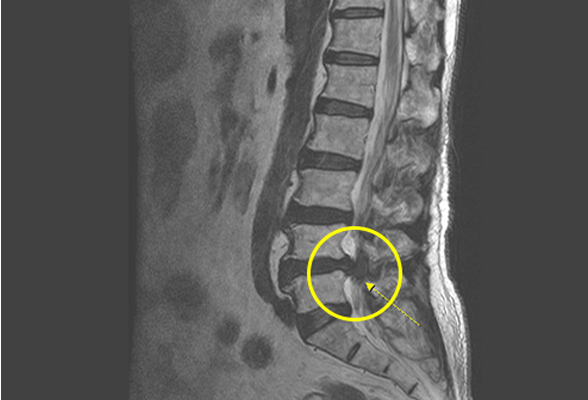

디스크내장증

디스크에 퇴행성 변화가 일어나면서 섬유륜이 약해져 균열이 가고 손상되는데,

이 부분에 혈관과 신경이 비정상적으로 자라 들어가 통증을 유발하는

질환을 디스크 내장증이라고 합니다. MRI 검사상 정상 디스크는 수핵 부분이

하얗게 보이나, 디스크 내장증이 있는 경우에는 검게 보이는 특징이 있습니다.

비수술 치료 : 약물치료, 도수치료, 신경차단주사, 경막 외 신경성형술, 풍선확장 신경성형술

수술치료 : 최소침습 척추유합술

허리에 통증이 지속되거나 반복 되기도 함